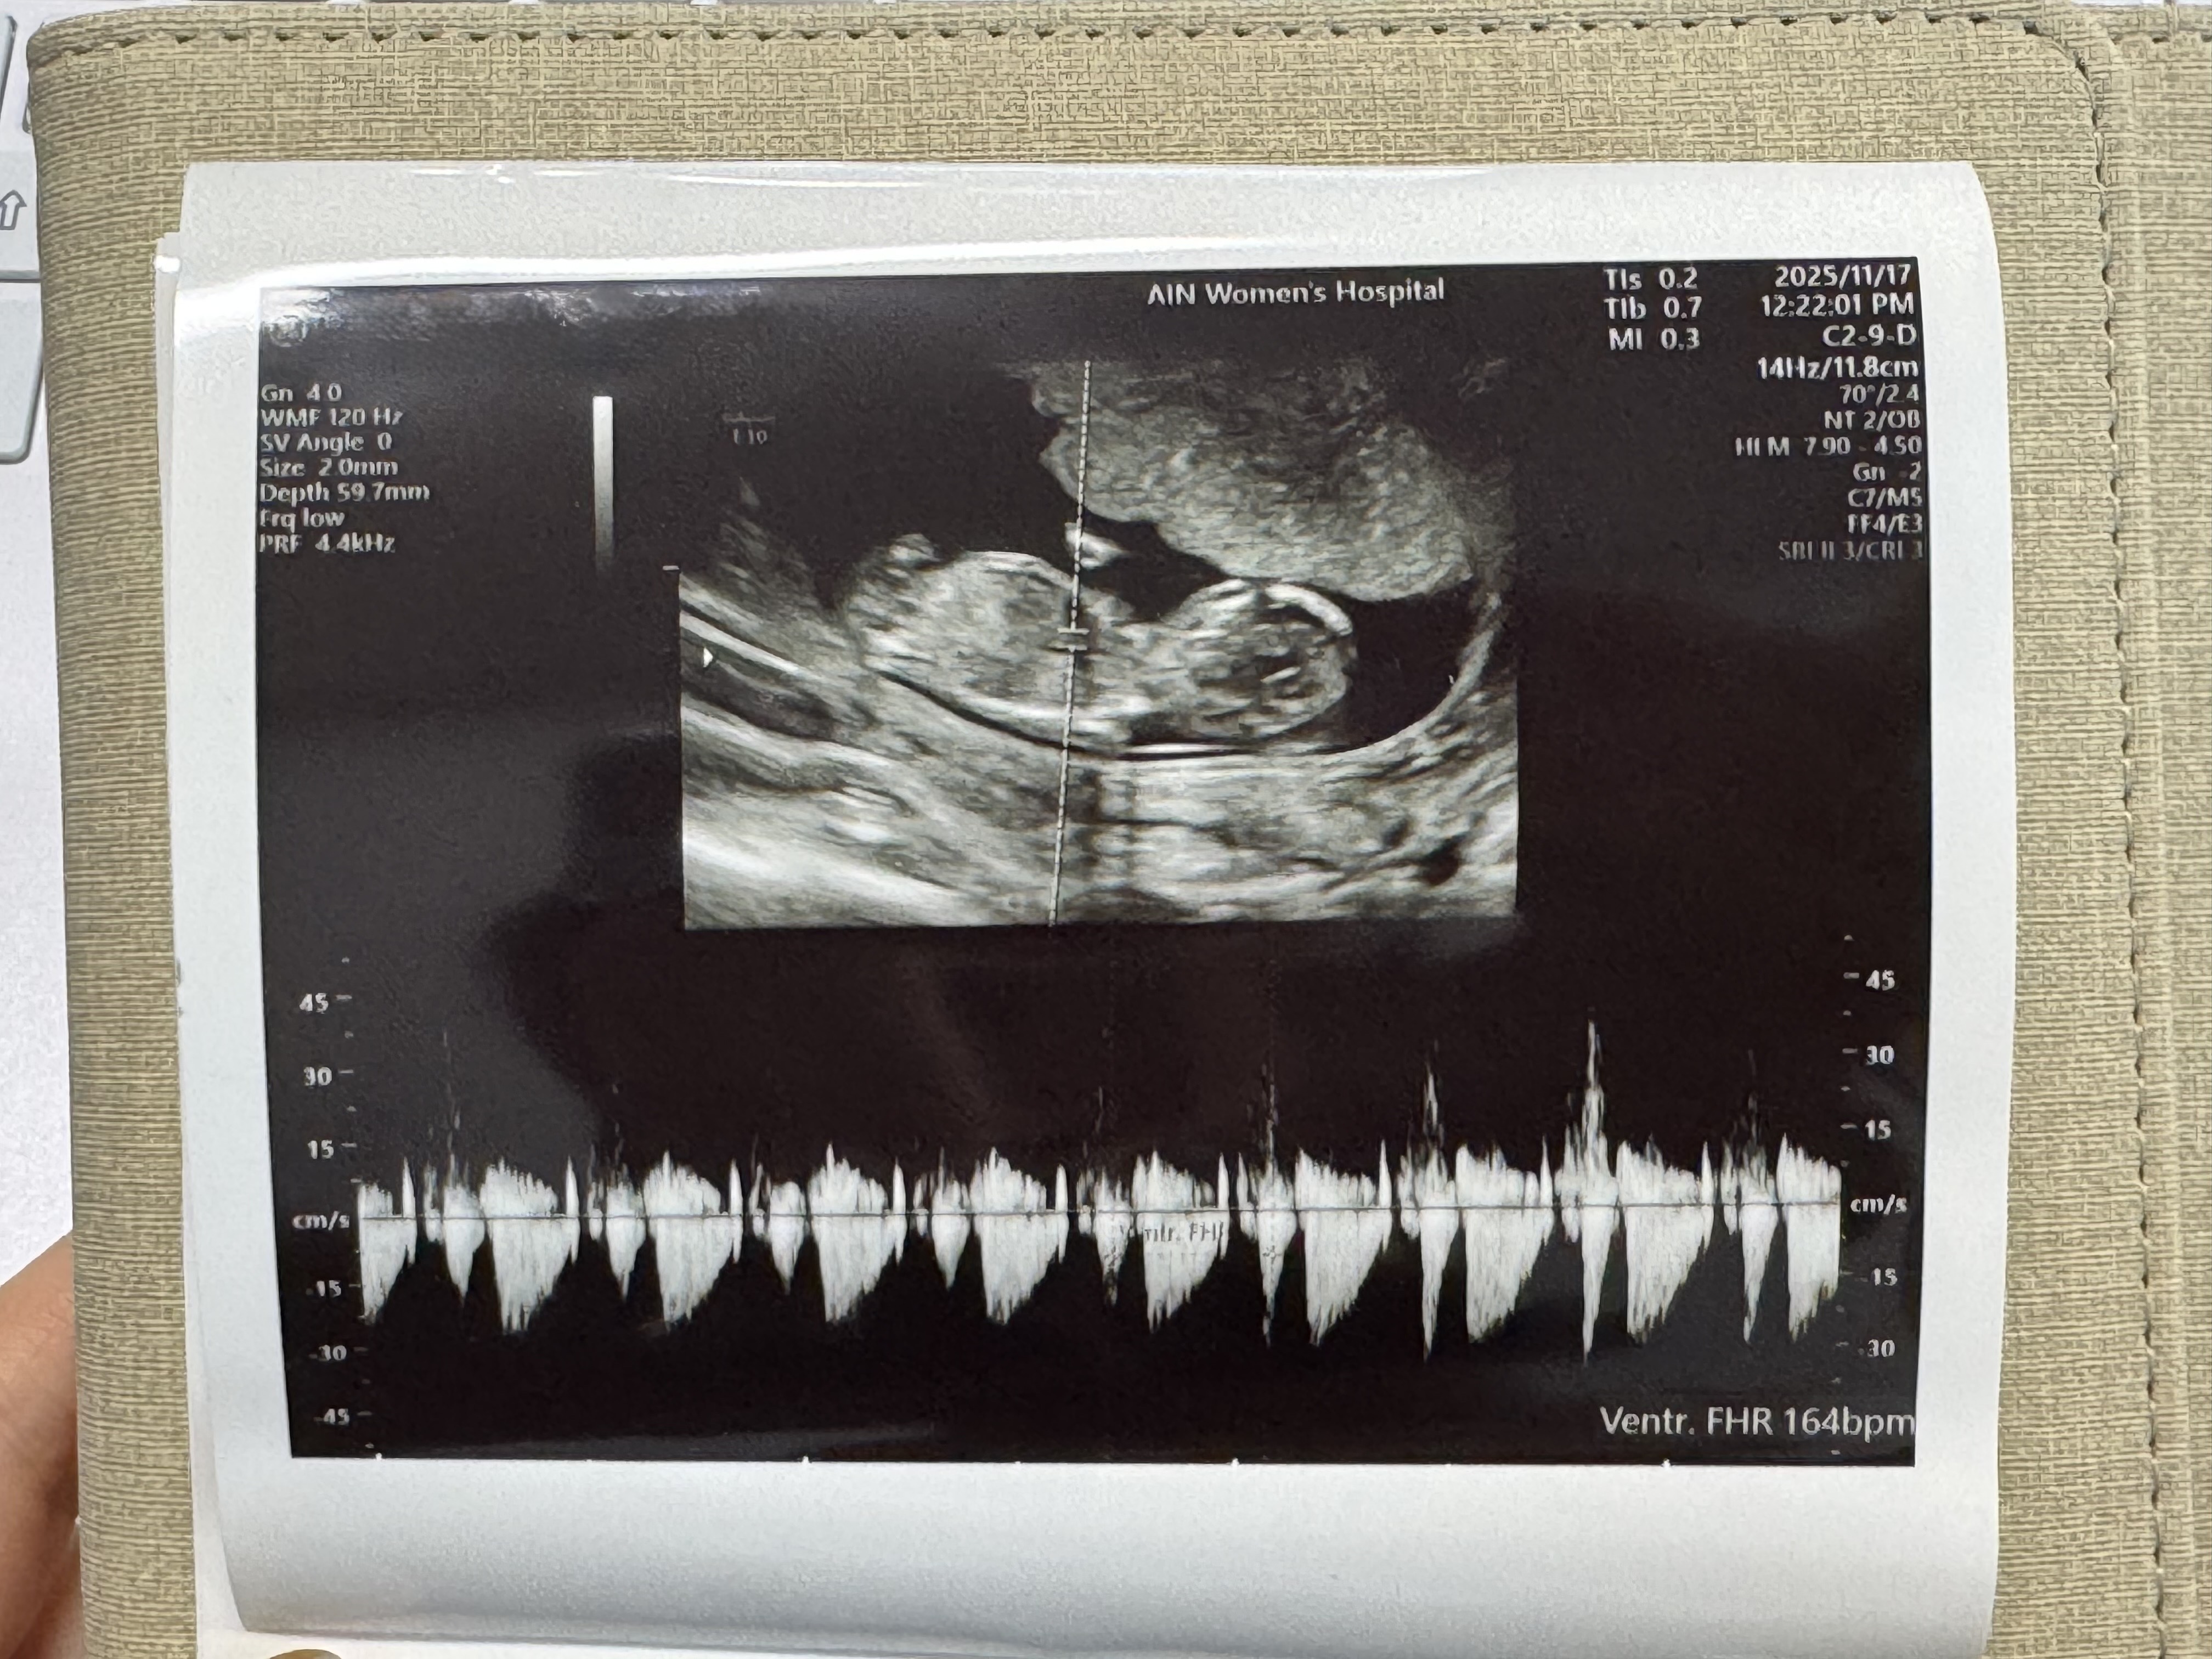

1차 기형아 검사하고 니프티도 하고왔어요

다행히 태반위치, 양수 다 좋고 목덜미두께도 1.34로 잘나왔더라고요 코뼈도 정상 ! 제가 나이가 딱 고위험군 산모이고 시험관해가지구 혹시나하는맘에 니프티 정밀검사도 해놓고왔어요..(!) 이제 궁금한건 성별인데 ㅋㅋㅋ다리를 꼬고있어서 더 모르겠고 아직 딸인지 아들인지도 잘 모르겠네요....😭 의사샘이 이제 운동해도된다해서 필라테스 곧 끊으러가려구요... 몸이 너무 찌뿌등했어요 슬슬 허리가 아프더라고요